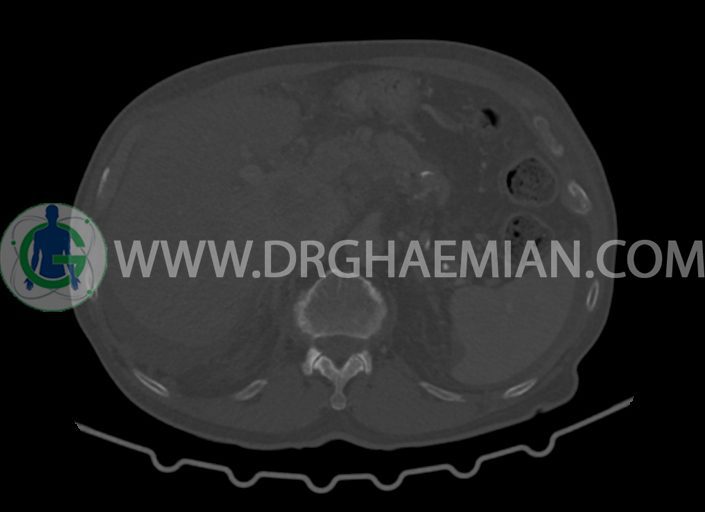

در سی تی اسکن اسپیرال شکم و لگن با کنتراست خوراکی و وریدی (مولتی دیدکتور 16 با مقاطع ظریف و بازسازی های ساژیتال و کرونال) :

-مایع آسیت با حجم Mild در ساب فرنیک دو طرف ، ساب هپاتیک و ساب اسپلنیک و اینترلوپ لگنپ

-کیست های کورتیکال ساده در هر دو کلیه به بزرگترین قطر 27mm در سمت چپ (بوسنیاک 1)

-کلسیفیکاسیون آئورت شکمی و شاخه های آن

-توده ی بزرگ با حدود لبوله به ابعاد 89x87x76mm در لوب چپ کبد همراه با گسترش اکستراکپسولار و

شواهد آتروفی لوب جپ کبد

-توده به قطر 33mm در سگمان 6 کبد

-توده ی هیپودنس به ابعاد 30x21mm در ورید پورت خارج کبدی مطرح کننده ی Tumor thrombosis

در ارتباط با ضایعات کبدی در درجه ی اول متاستاز مطرح است. در تشخیص افتراقی با توجه به آتروفی لوب

چپ، mass forming cholangiocarcinoma نیز مطرح می گردد.